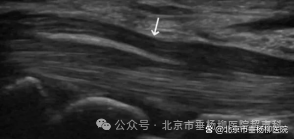

➭ 超声引导:在超声影像的实时监控下,医生将治疗器械(如注射针头)精确地插入病变部位。超声波提供的实时动态影像,使医生能够清晰地观察到治疗器械的位置和周围的组织结构。